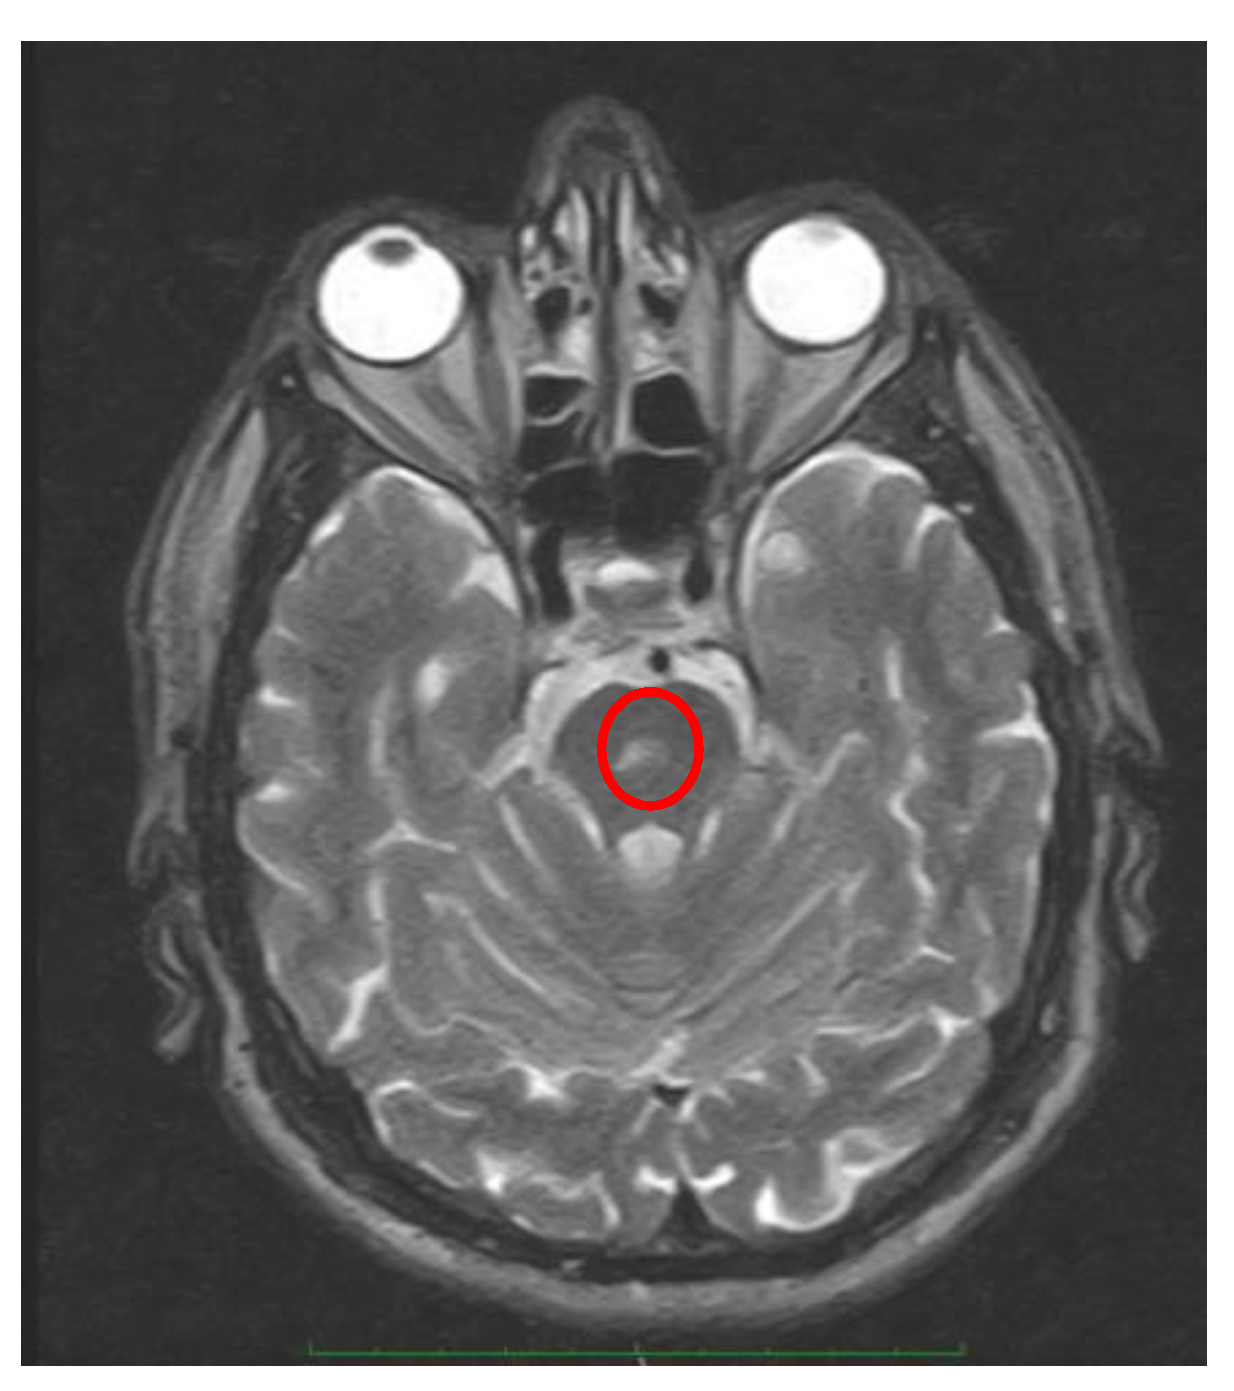

- Positional downbeating nystagmus (PDN). While in the past the presence of PDN during the head- hanging position and/or in Dix-Hallpike was considered a sign of central vestibular involvement, at the present time PDN is more frequently associated to an apogeotropic variant of posterior canal BPPV [56] or anterior canal BPPV [57]. Two patterns of PDN can be recognized: paroxysmal, with poor or no latency, duration less than 1 minute, and occasionally with a upbeating nystagmus when the patient return to the sitting position reversal; persistent, sometimes preceded by a paroxysmal component [58]. The pathophysiology of PDN during a brainstem lesion is similar to that described for the apogeotropic horizontal positional nystagmus. Recently a case of paroxysmal CPN mimicking posterior canal BPPV was described due to a pontine infarction [59]. Finally, upbeating nystagmus and central bidirectional geotropic nystagmus of central origine are much rarer.